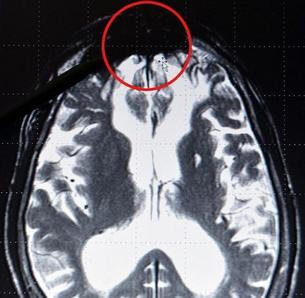

Při testech aplikovaných na skupinu zločinců, odsouzených za ty nejbrutálnější prohřešky, dospěli k velmi zajímavým závěrům. Ty však byly následně v médiích zkomoleny – hlásal se objev „centra zla“ v temenním mozkovém laloku.

Nic takového samozřejmě neexistuje. Týmu se nicméně podařilo prokázat, že někteří jedinci nereagují na projevy brutality stejně jako většina populace. Výše zmíněné skupině zločinců promítali násilné záběry a sledovali přitom jejich mozkové vlny.

V místě, kde se za normálních okolností projevují emoce, jako je lítost či soucit, zůstalo u těchto jedinců při promítání prázdné místo, jako by bylo vyplněno temnou hmotou. Jejich mozek prostě na něco, co se většině populace příčí, vůbec nereagoval.